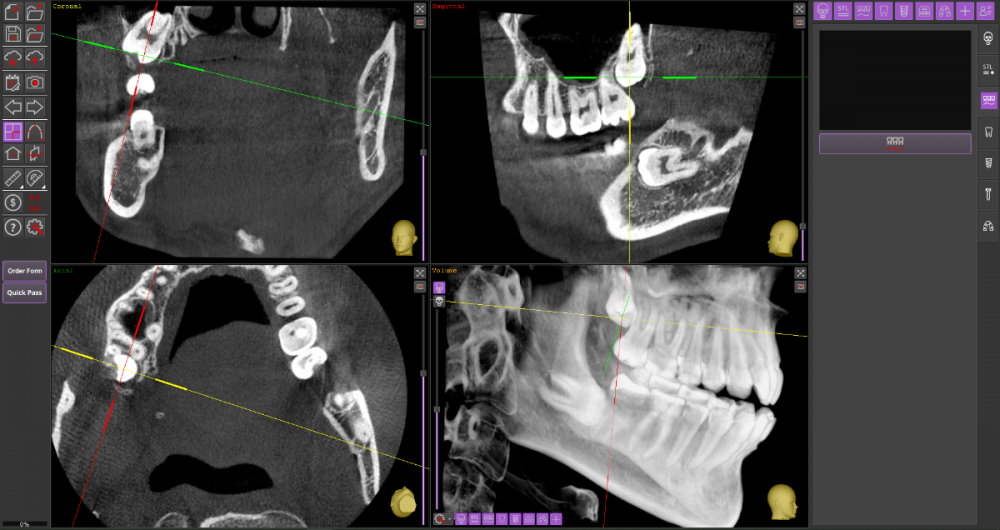

Прошу Вашего совета по поводу удаления восьмых зубов.

Из жалоб есть непродолжительная ноющая боль в правой нижней челюсти, не связанная с внешними раздражителями.

1. Необходимо ли удаление зубов мудрости?

2. Возможно ли удаление амбулаторно, без общего наркоза?

3. Нет ли риска для семёрок при удалении.

46_1.thumb.png.bd3e8803a4ef0e1ca17a622107948968.png

48_1.thumb.png.e7ba39d8dfa64bdaaa4a74e42f1e980d.png

48_2.thumb.png.7e20efc1b8eb4a26c5acf66b896d88a6.png

Виновником боли в н.ч. справа может быть, например зуб 46, не только 48.

1. Удаление 8-х зубов скорее всего необходимо

2. Удаление амбулаторно вполне возможно. Общая анестезия (наркоз) совершенно необязательна, местной анестезии достаточно.

3. Несчастные случаи бывают, но крайне редко.